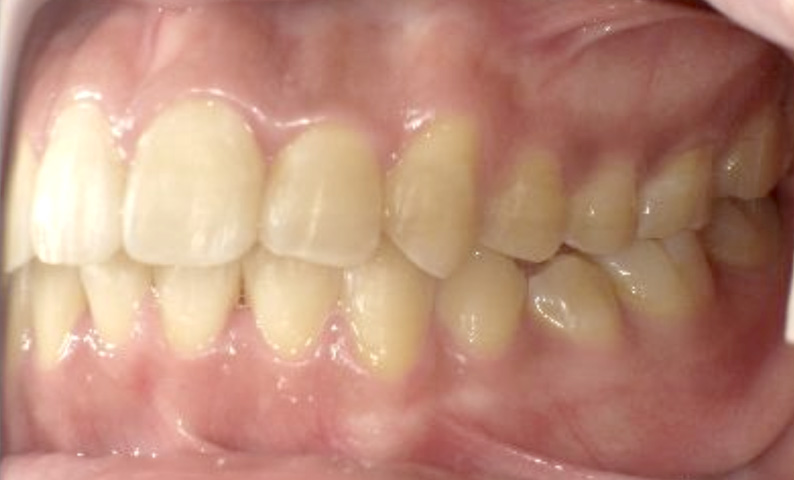

症例_025 上下顎の部分矯正

治療期間:13ヶ月金額:51万円+税女性前歯のガタガタ出っ歯

| Before | After |

|---|---|

|